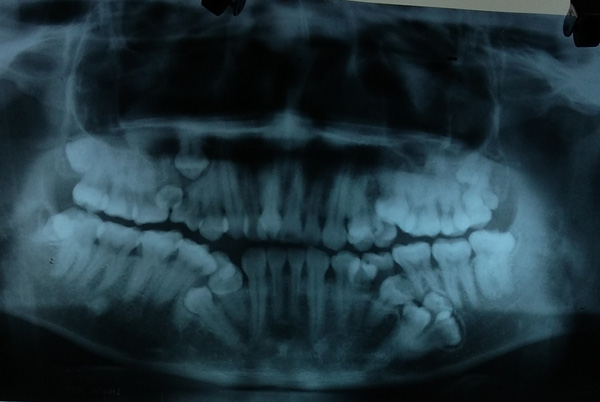

Bệnh nhân là Đỗ Văn Sơn (28 tuổi, Quốc Oai, Hà Nội). Anh Sơn cho biết, từ năm 15 tuổi đến nay, cứ mỗi năm anh lại thấy mọc thêm 1 chiếc răng. Nghĩ là mọc lẫy bình thường, lại không đau đớn nên anh không hề đi khám.

Cách đây 10 ngày, thấy răng sâu ở hàm trên đau nhức khó chịu, anh mới đến Bệnh viện Việt Nam – Cu Ba khám.

Tại đây các bác sĩ đã hết sức bất ngờ khi phát hiện ngoài chiếc răng sâu, bệnh nhân bị mọc thừa đến 13 chiếc răng ở vị trí răng 4 và 5 trên 2 hàm.

Các răng mọc lệch, chen chúc, dàn hàng ngang khiến việc vệ sinh khó khăn, gây sâu, viêm tủy.

Theo BS Nguyễn Thanh Thái, Trưởng khoa Phẫu thuật Tạo hình Hàm mặt, sau khi chỉ định chụp CT, panorama, các bác sĩ lại tiếp tục phát hiện thêm bệnh nhân có 4 mầm răng chưa mọc.

Hiện bệnh nhân đã được điều trị tủy dứt cơn đau răng, đồng thời làm xét nghiệm để chuẩn bị mổ bỏ các răng thừa vào tuần tới.

"Hiện tượng mọc thừa răng không phải chuyện lạ, tuy nhiên bình thường chỉ thừa 1-2, nhiều lắm thì 3 chiếc. Trường hợp nhiều nhất chúng tôi từng gặp là thừa 8 răng nhưng trường hợp thừa 17 răng như anh Sơn thì chưa từng gặp”, BS Thái nói.

BS Thái khuyến cáo, người dân nên có thói quen khám răng định kỳ 6 tháng 1 lần. Khi thấy răng mọc 2-3 cái một chỗ cần đi khám ngay để can thiệp kịp thời.

Trường hợp răng thừa để lâu sẽ làm xô lệch các răng khác, dễ dắt thức ăn, vệ sinh khó khăn gây sâu, viêm tuỷ, viêm lợi./.